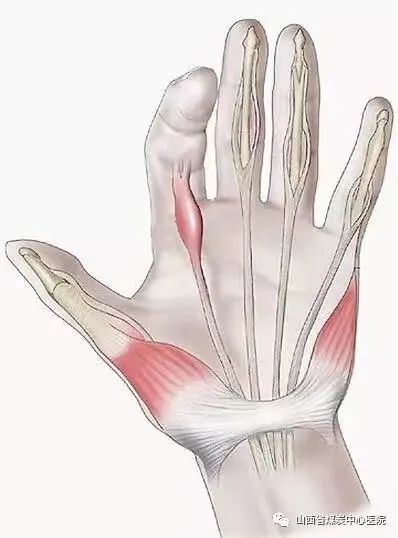

山西省煤炭中心医院已经获批“山西省超声可视化针刀培训中心”,系全国首家省级可视化针刀培训中心,将进一步推动我省乃至全国超声可视化针刀诊疗规范化、标准化、同质化,促进可视化微创诊疗技术水平的提升和发展。超声引导下针刀治疗就是可视化针刀微创技术,治疗的那根针就是针刀——由金属材料做成的在形状上似针又似刀的一种用具。其尾部为柄,体部为针,头部为刀。针刀虽小,作用很大,超声为针刀技术装上了“眼睛”,使针刀治疗更加精准、安全。可视化时代的针刀微创技术是针刀医生的GPS和“第三只眼”,它将术前明确诊断、术中精准引导靶点松解,术后进行评估,避免肌腱、神经、血管等组织损伤,减少治疗次数(每周一次)、缩短患者病程、保障医疗安全、大幅度提高临床效果

超声可视化针刀微创诊疗技术主要解决各类疼痛及偏瘫类疾病。一、脊柱疾病如颈椎病、腰椎间盘突出症等;关节疾病如膝关节骨性关节炎;各种软组织损伤如肩周炎、网球肘、梨状肌损伤;神经卡压如腕管综合征等疾病;腱鞘炎;鼻炎;带状疱疹等,主要原理:消炎(无菌性炎症);松解粘连;改善肌肉平衡。二、脑梗死、脑出血、脑外伤、脊髓损伤等引起的偏瘫、四肢瘫。主要原理:醒脑调衡;神经调控术;缓解或解除肌痉挛等。山西省煤炭中心医院